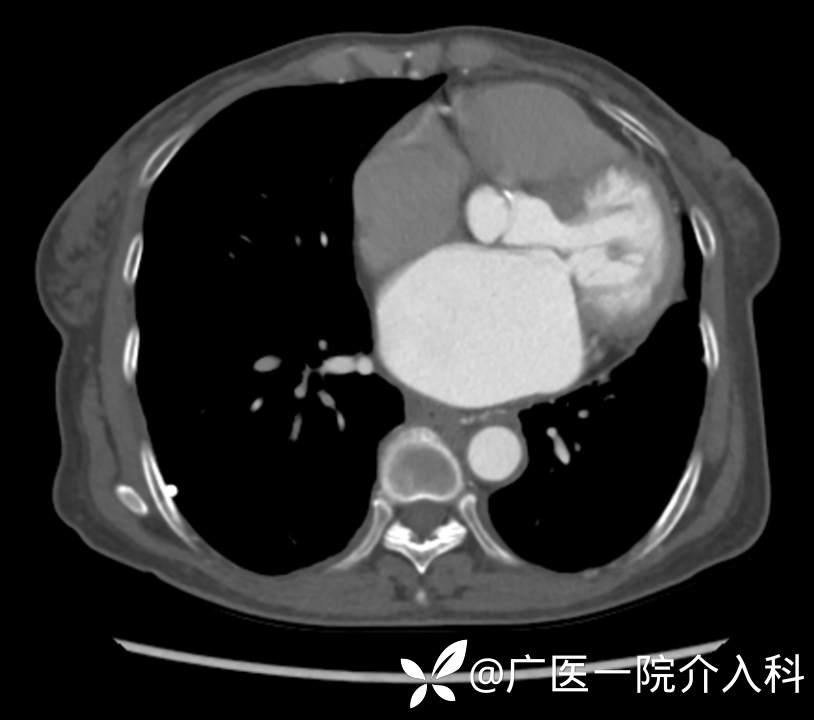

既往病史:乙肝病史20余年。3个月前开始胸闷气促,外院胸腔CT提示右侧胸腔积液,行胸腔置管,症状后有缓解。在我院复查增多胸水,经多次抗炎治疗未见明显效果。查体及影像学证实肝硬化伴食管胃底静脉曲张。患者去年5月因消瘦入院,诊断为肝硬化伴食管胃底静脉曲张,已行3次食管胃底静脉套扎术。

术前置管引流下的右侧胸水,如上箭头